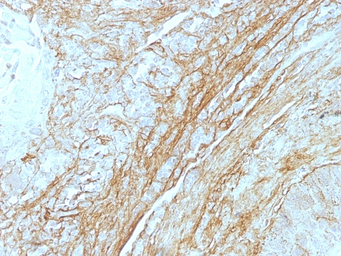

IHC-P analysis of human lung carcinoma tissue using GTX35097 Tenascin C antibody [T2H5].

Tenascin C

Tenascin C antibody [T2H5]